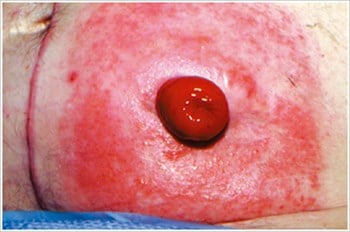

Pyoderma Gangrenosum3

Description/causes : Une maladie inflammatoire de la peau souvent observée chez les patients atteints d’une maladie inflammatoire de l’intestin (MII) telle que la maladie de Crohn ou la colite ulcéreuse.

Symptômes : Ulcères irréguliers, rouges, douloureux, infectés, avec des marges roulées rouges à violettes ; apparaissent sur les jambes, les fesses, le visage et la région péristomiale.